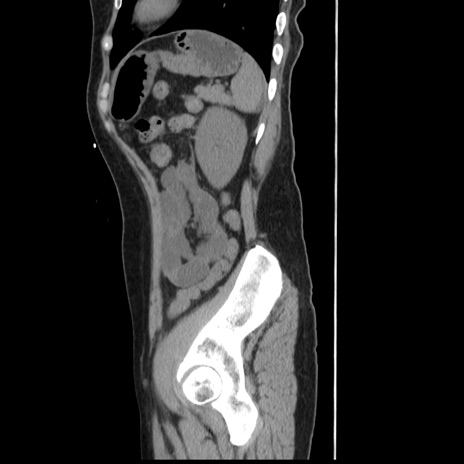

冠状断像

【症例】 50歳代女性

【主訴】 腹痛

【現病歴】前日生レバーを食べた。今朝に排便あり。 昼前に突然発症の腹痛を生じ、当院救急外来を受診した。

【既往歴】 子宮筋腫にてで子宮全摘後

【身体所見】 意識清明、腹部:平坦、軟、下腹部やや左を中心に圧痛・反跳痛あり、筋性防御あり

【データ】WBC 7800、CRP 0.07